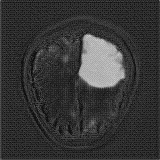

We obtain a slice-wise mean Dice score of 32.24% for this liver lesion segmentation, which improves to 50.23% by using a simple post processing scheme of erosion and dilation with filter. Sampled results are shown in Fig. 4. Compared with [42], which obtains a mean Dice score of 40.78% and a standard deviation of 0.43%, we improve the mean Dice score by almost 10%, but has a much larger standard deviation. Unlike [42], where the network is pre-trained on a artificial tumor dataset, and hence the pipeline customized for tumor segmentation, our method do not need such information beforehand. We notice that our standard deviation for BraTS dataset is similar to [27]. This is because novelty/anomaly detection algorithms without a pre-defined task would suffer from the co-morbidities issues discussed in Section 5.

Our method still has room to improve, compared with supervised methods. A recent study [14] reports a cross-validation result of 67.3% under a supervised setting. Note that the annotation in the LiTS lesion dataset is imperfect with missing small lesions [11, 14]. Since we use the imperfect annotation to select images for the reference distribution, some slices with small lesions may be included and treated as normal examples. Also, the faint liver boundary causes a fixed penalty to be incurred per slice, which reduces the dice score. This kind of segmentation noise could be better handled by using a more sophisticated post-processing strategy.